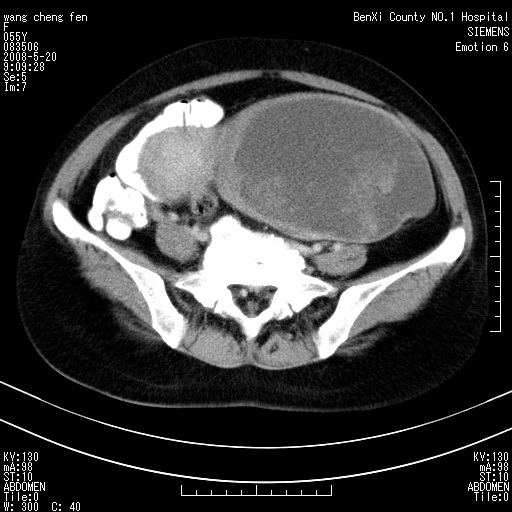

女、绝经后阴道流血3个月

左侧附件区巨大囊实性病灶,边缘光整,病灶囊壁较厚,增强示囊壁及实性部分明显强化,强化呈度与宫体实质大致相同,宫腔积液征像,未见盆腔积液等其他异常,考虑左侧卵巢囊腺癌,不除外囊腺瘤及浆膜下肌瘤坏死

左侧附件区巨大囊实性病灶,边缘光整,病灶囊壁较厚,增强示囊壁及实性部分明显强化,强化呈度与宫体实质大致相同,宫腔积液征像,未见盆腔积液等其他异常。绝经后阴道流血3个月,结合病史左侧卵巢囊腺癌首先考虑,宫腔扩大不除外累及。期待结果。

支持浆膜下子宫肌瘤.之前由于网络原因未看全图片,现在重看,宫颈见一类圆形低密度影,增强轻度强化,低于肌层强化,宫腔扩大,考虑宫颈癌伴宫腔积液可能性大.

考虑巨大的浆膜下子宫肌瘤并变性坏死,宫颈周围静脉曲张。

1,宫颈部占位,宫颈癌?2,左侧附件区囊实性占位,界较清,实质部分强化明显。考虑浆膜下或阔韧带肌瘤囊变可能大。囊腺类肿瘤不除外。